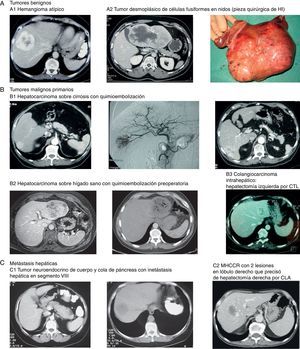

Imágenes de algunos tumores de nuestra casuística. A) Tumores benignos. 1) Hemangioma atípico. 2 y 3) Tumor desmoplásico de células fusiformes en nidos (pieza quirúrgica de HI). B) Tumores malignos primarios. 1) Hepatocarcinoma sobre cirrosis con QME. 2) Hepatocarcinoma sobre hígado sano con quimioembolización preoperatoria. 3) Colangiocarcinoma intrahepático que requirió hepatectomía izquierda por CTL. C) Metástasis hepáticas. 1) Tumor neuroendocrino de cuerpo y cola de páncreas con metástasis hepática en segmento viii. 2) MHCCR con 2 lesiones en lóbulo derecho que precisó de hepatectomía derecha por CLA.